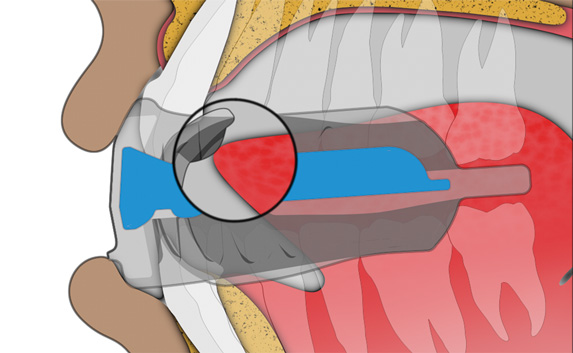

Tongue tag

encourages correct tip of the tongue positioning.

Tongue elevator

encourages the body of the tongue to rest in the roof of the mouth.